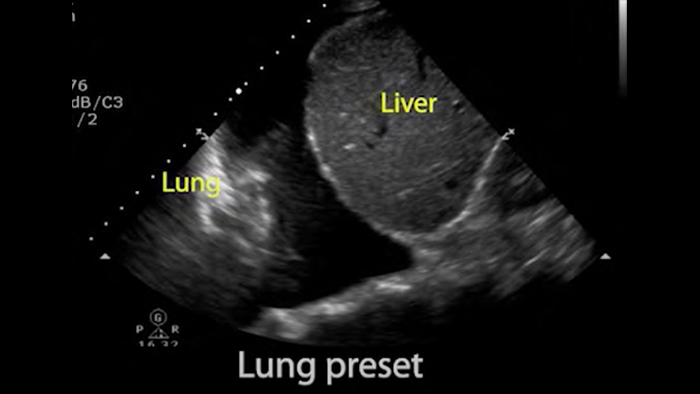

• Расширенный диапазон рабочих частот — от 4 до 1 МГц. • 2D, цветной доплеровский режим, M-режим, продвинутая визуализация XRES и многомерная гармоническая визуализация. • Визуализация с высоким разрешением для брюшной полости и сердца: предустановленные оптимальные режимы визуализации для сердца, легких, брюшной полости, диагностики в акушерстве/гинекологии и режим FAST.

Lumify может помочь вам принимать решения в режиме реального времени с большей уверенностью, от первичной диагностики до выздоровления. Раскройте тонкие детали изображения, изучите мельчайшие структуры ткани под несколькими углами и многое другое.